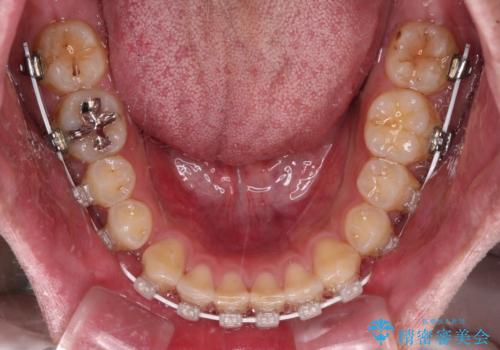

深い咬み合わせと隙間の空いた歯列をワイヤー矯正で改善

- 審美装置

マウスピース矯正の自己管理が面倒とのことで、ワイヤー矯正により治療を行うこととしました。

奥歯の咬み合わせは理想的な状態であったため、ワイヤー矯正でもインビザラインでも比較的容易に対応可能でした。